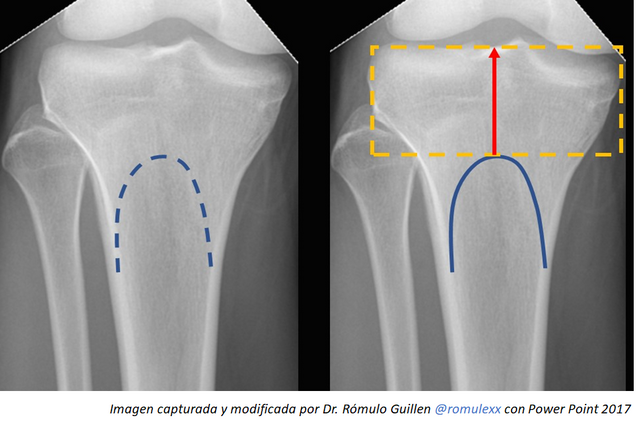

Nuevo método de determinación radiológica de las dimensiones de la epífisis tibial proximal en población adulta

El Doctor @romulexx nos presenta de manera detallada un procedimiento, desde el punto de vista radiológico, para la determinación de la dimensión proximal de la tibia que corresponde absolutamente al hueso trabecular, realiza un estudio comparativo entre 55 hombres y 55 mujeres para así obtener estos resultados médicos-estadísticos con una precisión aceptable. Se espera que la información de este estudio se puedan implementar en pacientes con lesiones en el área proximal de la tibia y aliviar cualquier traumatología en esa zona del cuerpo. Por su aporte de conocimientos inéditos ocupa el Primer Puesto del Podio de la comunidad #stem-espanol.

Sin duda alguna me siento muy honrado de haber sido tomado en cuenta y por calificarme en el primer lugar esta semana con mi aporte, cabe destacar que ese trabajo científico se encuentra aun estudiándose, y que pronto sera publicado en una revista cientifica, sin embargo quiero dar méritos a @stem-espanol y a @steemstem por el excelente trabajo que realizan apoyando a la comunidad cientifica y a los queridos lectores